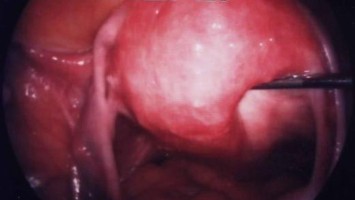

Operative Konzepte für die Therapie der Endometriose

Die operative Therapie der Endometriose ist anspruchsvoll. Sie reicht von der Resektion oberflächlicher peritonealer Herde bis zur interdisziplinären Operation mit partiellen Organresektionen an Darm, Blase, Urogenitaltrakt und Zwerchfell. Die …

Endometriose und Kinderwunsch – wann operieren, wann nicht?

Eine Operation kann auch bei Endometriose-Patientinnen mit unerfülltem Kinderwunsch der richtige therapeutische Schritt sein. Allerdings ist der optimale Zeitpunkt vom Stand der Familienplanung, Lebensalter und der bisherigen Vorgeschichte abhängig. Rein diagnostische Operationen sind obsolet und sollten idealerweise vermieden werden.